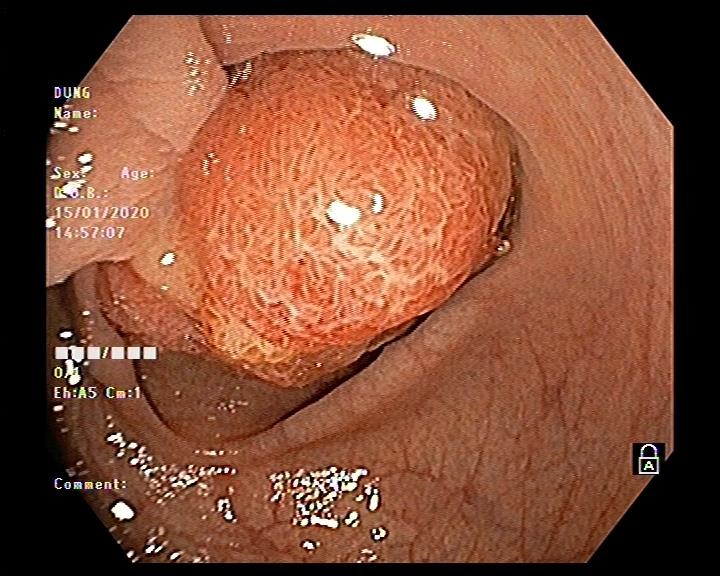

Bệnh nhân nam 61 tuổi đi khám bệnh tại Bệnh viện đa khoa tỉnh Hải Dương vì lý do đi ngoài ra máu. Bệnh nhân được bác sĩ khám và cho chỉ định nội soi đại tràng. Trong quá trình nội soi phát hiện ở đại tràng sigma có 01 polyp lớn khoảng 2,5 cm có cuống lớn và dài. Bệnh nhân có chỉ định cắt polyp phòng ngừa nguy cơ polyp ung thư hóa.

Hình ảnh nội soi đại tràng cắt polyp

Vấn đề đặt ra là với kích thước và tính chất polyp như vậy thì có khả năng polyp được nuôi bằng mạch máu lớn, nếu chỉ cắt đốt bằng phương pháp thông thường thì nguy cơ xuất huyết ồ ạt sẽ rất cao. Do đó bác sĩ nội soi Ths Vũ Thanh Tùng quyết định sử dụng vòng Endoloop để thắt cuống polyp trước khi tiến hành cắt đốt. Thủ thuật diễn ra thuận lợi, nhanh gọn trong vòng 10-15 phút và không xảy ra tai biến dù là polyp này được nuôi bằng mạch máu lớn.